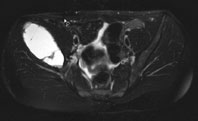

Die Röntgenuntersuchung von Becken/Hüfte zeigt eine septierte geographische Osteolyse in der Ala und im Korpus des Os Iliums rechts. Das Röntgenbild und die Aufnahmen der nachfolgenden MRI-Untersuchung sehen Sie hier: